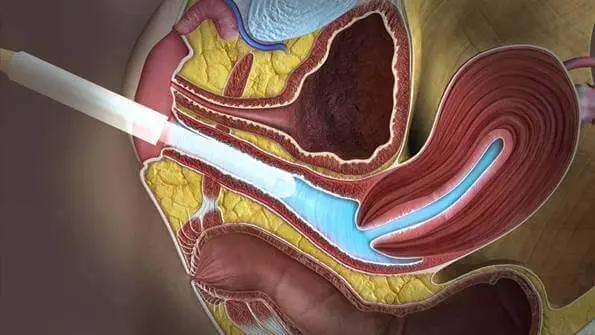

Трансвагінальний доступ є “золотим стандартом” в дослідженні органів малого таза на увазі найкращою візуалізації з найтоншої оцінкою структури, оптимальний метод в діагностиці вагітності на ранніх термінах, оцінці будови плода до 14 тижнів. Датчик розташовується в піхві.